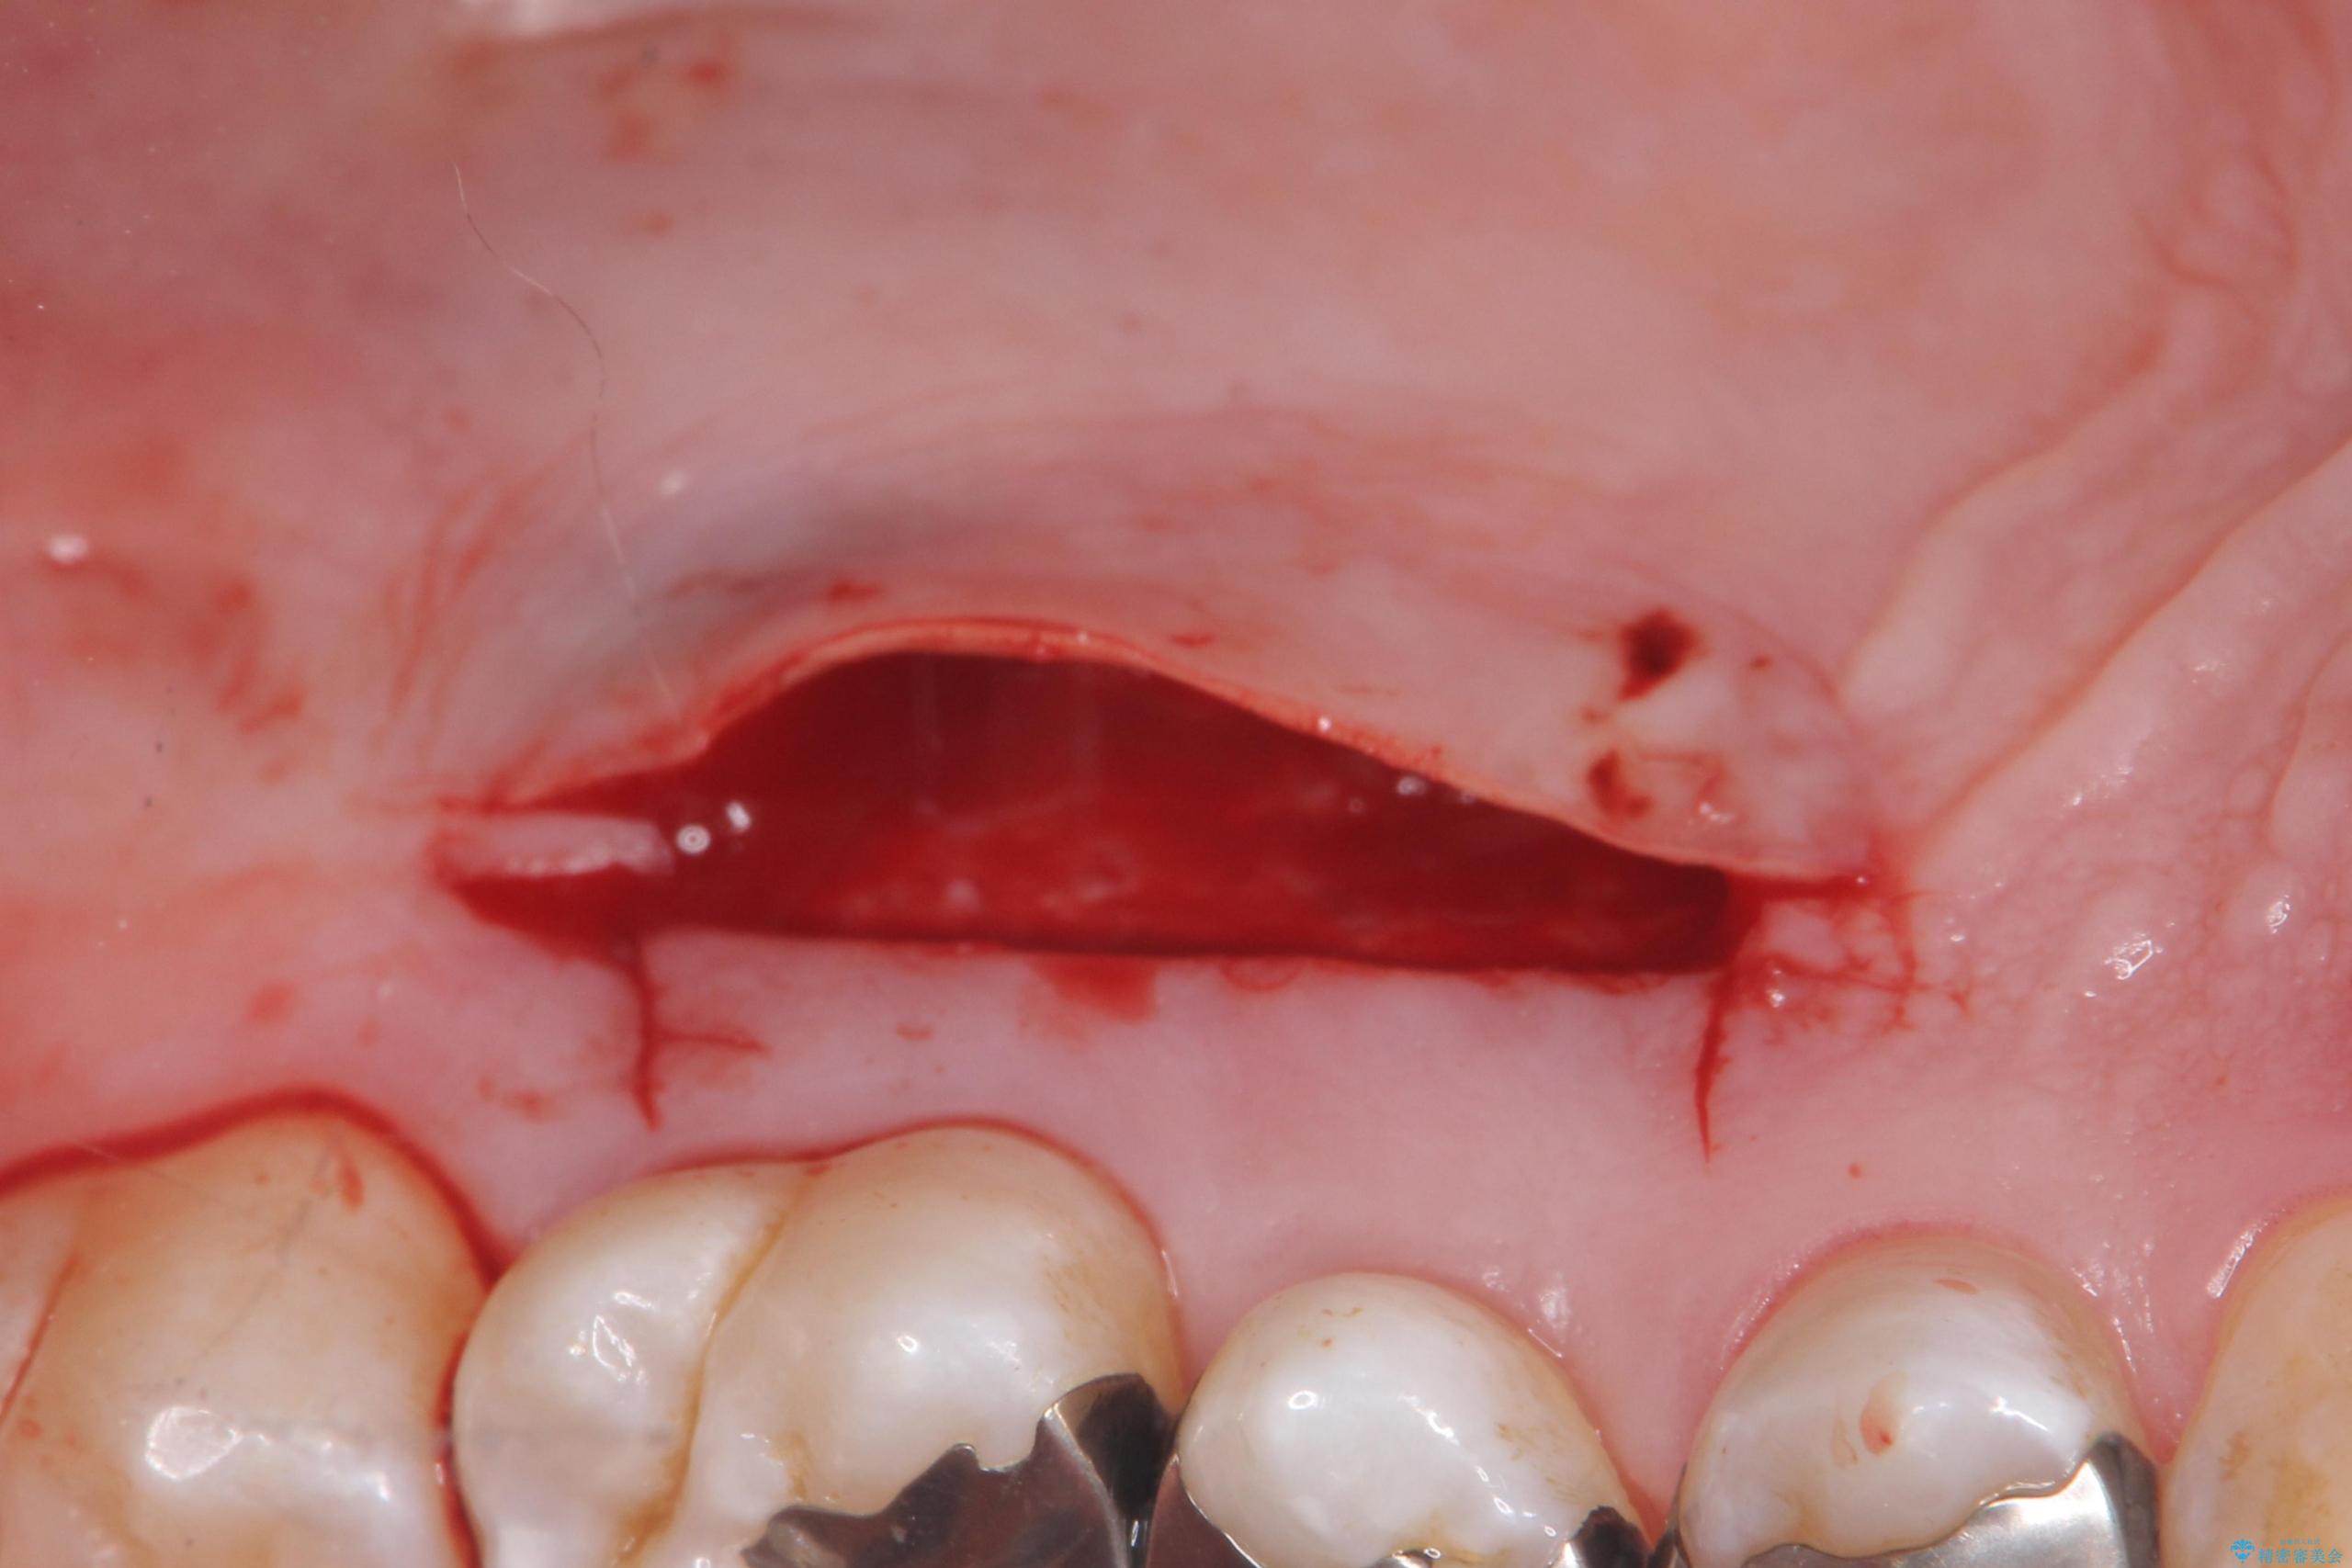

退縮した歯茎に対して移植をすることで、しみる場所を覆う計画です。

歯根の分岐部よりも根尖側の頬側面が露出している状態でしたが、露出部位を分岐部までに抑えることができました。